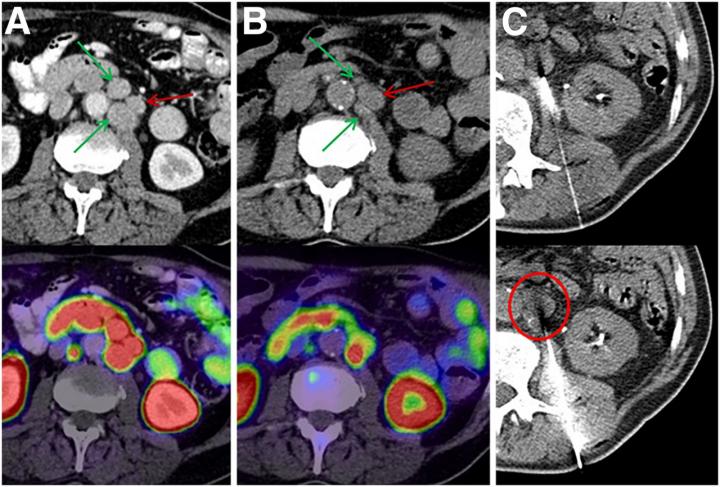

Intra-patient tumor heterogeneity makes tissue sampling of the most appropriate index lesion challenging. (A) Baseline PSMA PET/CT demonstrated group of 3 lymph nodes with homogeneously intense uptake with SUVs of 29.7-35.5 (arrows). (B) After 225Ac-PSMA therapy, 2 lesions with SUVs of 29.7 and 32.0 showed morphologic response (green arrows), but index lesion with highest initial uptake (SUV, 35.5) had increased size (red arrow) and persisting PSMA uptake (SUV, 30.0). (C) This lesion (encircled) was chosen for imaging-guided biopsy.

Images created by C Kratochwil and CP Heussel et al., University Hospital Heidelberg, Germany.